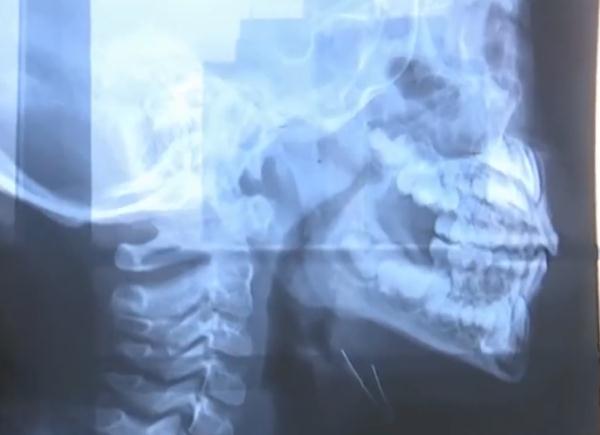

經(jīng)過醫(yī)生檢查

這名男孩是腺樣體肥大導(dǎo)致鼻子不通氣

習(xí)慣以口呼吸方式

代替鼻呼吸

自己的孫女剛做完腺樣體肥大手術(shù)

檢查后是因?yàn)橄贅芋w肥大

兒童腺樣體肥大導(dǎo)致口呼吸癥狀

在幼童群體中很普遍

一般來說腺樣體肥大超過三分之二

會(huì)影響孩子鼻呼吸

建議手術(shù)調(diào)節(jié)